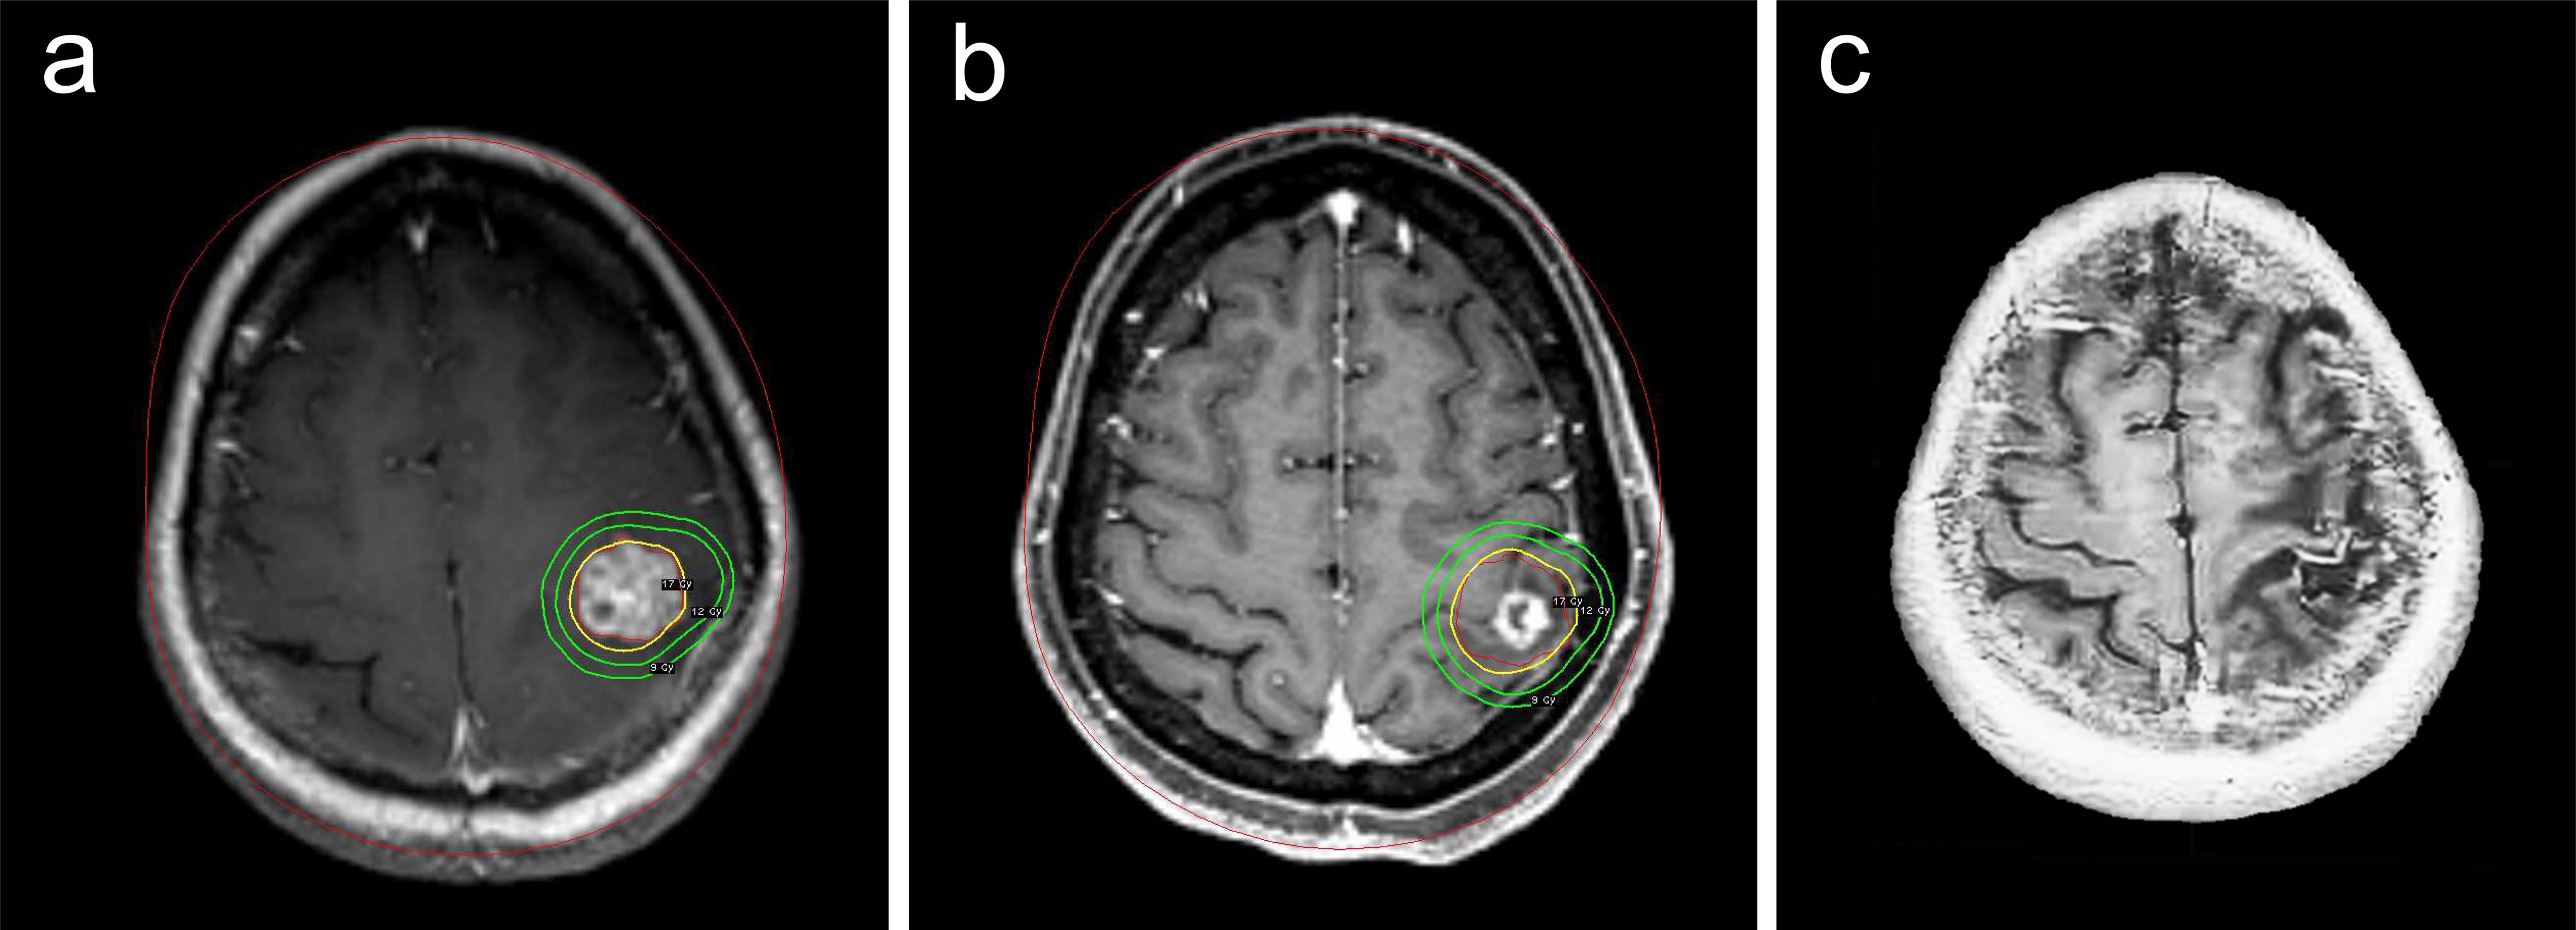

At the 12-month follow-up, 68 metastatic lesions were assessed: 32 (47.1%) achieved CR, 20 (29.4%) showed PR, 14 (20.6%) remained SD, and two (2.9%) showed PD. The tumor control rate was 97.1%. No tumor hemorrhage was observed following GKSRS. Figure 2 illustrates a representative case in which a female patient experienced a significant reduction in tumor size following GKSRS treatment.

Axial-loaded MRI of a 52-year-old female patient with right limb weakness.

Fig. 2  Axial-loaded MRI of a 52-year-old female patient with right limb weakness.

She underwent GKSRS for brain metastasis from ovarian cancer on May 14, 2019. The central and peripheral doses were 34 Gy and 17 Gy, respectively, with a 50% isodose line (a). A follow-up MRI on December 19, 2019, revealed a reduction in tumor size, and her right limb weakness gradually improved (b). A subsequent MRI on February 15, 2025, confirmed continued tumor shrinkage (c). GKSRS, Gamma Knife stereotactic radiosurgery; MRI, magnetic resonance imaging.